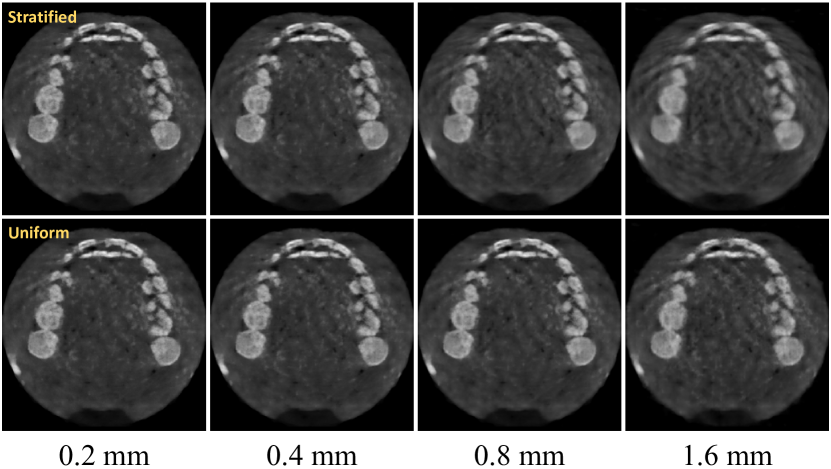

Refer to caption

Figure 6: Visual comparison of sampling strategies with various marching steps.

Sampling strategies are crucial in learning attenuation fields. In our SNAF, we adopt the simple uniform sampling strategy with a marching step D𝐷D, although stratified sampling is an alternative solution. In this experiment, we validate our choice.

Varying the marching step D𝐷D. It is clear that a bigger D𝐷D means fewer sampling points along a ray. With fewer points, it tends not to cover the entire space very well, but significantly simplifies the calculation. As can be seen from Tab. 2, when we increase D𝐷D from 0.2mm0.2mm0.2\text{mm} to 0.8mm0.8mm0.8\text{mm}, marginal performance degradation is observed (30.86 vs. 30.63 for PSNR), while only less than 1/3 of the training time is required. Visual examples in Fig. 6 also validates this point. Thus, to trade off the training time and reconstruction quality, we can properly and faithfully enlarge the marching step D𝐷D, and D=0.2mm𝐷0.2mmD=0.2\text{mm} is used in our algorithm to first ensure reconstruction quality.

Uniform vs. stratified sampling. We validate that the uniform sampling is the best fit in our attenuation field learning by comparing with the alternative stratified sampling scheme with increasing D𝐷D values. As can be seen from Tab. 2 and Fig. 6, when we use smaller D𝐷D, uniform sampling is on par with stratified sampling. However, large D𝐷D, e.g., 1.6mm1.6mm1.6\text{mm}, will bring noticeable artifacts and significant decreasing in terms of PSNR (i.e., 29.73 vs. 28.95). The reasons are that, first, our final goal is to acquire a discrete representation (i.e., 3D volume) by grid sampling, rather than a completely continuous radiance field for generating novel views. It is reasonable to keep a fixed sampling step to capture this explicit 3D volume. Second, uniform sampling allows integration of total variation loss along the ray, avoiding the streaking artifacts. Instead, the randomness introduced by the stratified sampling cannot produce sample points that are evenly distributed within the volume. We thus conclude that uniform sampling is the best sampling strategy in learning neural attenuation fields.